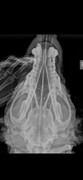

Добрый день. Сегодня были на УЗИ и на приеме у Курзиной. По сердцу противопоказаний нет .Сделали рентген головы и здесь всё плохо , нужно МРТ у старушки на рентгене обнаружили тёмные пятна ,нужно срочно сделать МРТ чтобы установить онкология это или скопление гноя это состояние болезненно для собаки. Если это гной то его нужно быдет выводить . Так же на МРТ мы увидим задета ли кость. Врач сказала, что собака мучается от боли и нужно срочно принимать решение.

Гной вытекает из ушей , на снимке мне показали места где скопился гной, но полную картину покажет мрт, задеты ли кости, и в каком состоянии мозг

Марина Васильевна назначила нам немного другие препараты по ушкам, так же назначили Цефтриаксон( уколы) . Посмотрел снимки Честяков ( хирург) скопление гноя в облости ушей подтвердил. Теперь мы будем промывать болтушкой, ее сдедали в клинике и колоть уколы . Отофа практически вся вытекает, а болтушка вливается со шприца прямо в ушную раковину курс 10 дней, а там посмотрим результаты.

Я бы не тратила деньги на МРТ. Даже людям при затяжных отитах МРТ всем подряд не назначают. Только если есть подозрение на воспаление мозга. Но тут симптомы очень явные и лечат сильными антибиотиками даже если МРТ никаких абсцессов в мозге не показывает.

Если видят скопление гноя на рентгене, я бы уточнила, для чего дополнительное исследование, изменится ли лечение, если будет выявлена жидкость в среднем или внутреннем ухе, будут ли оперировать собаку, если разрушение кости есть. Если однозначно нет, смысла делать диагностику дополнительную нет.

Если все-таки думают оперировать, то делают КТ, МРТ не используют для диагностики разрушения костей черепа.

Для пожилых животных МРТ вообще не желательно, так как требует длительного наркоза, минимум 30 минут, а если с контрастом делать, то ещё и хороших показателей работы почек, что у пожилых животных редко. Предпочтение отдают КТ, которую можно сделать за 2 минуты под легкой анестезией